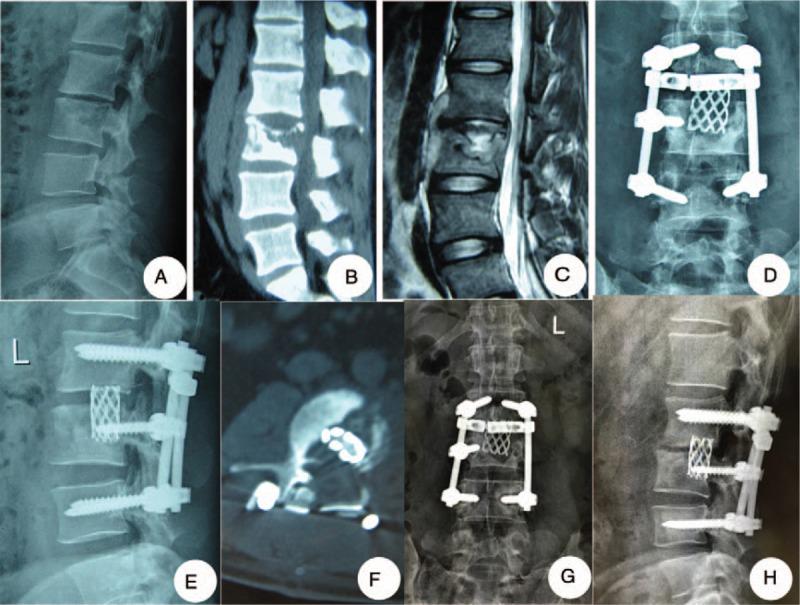

Surgical intervention is an important option for treating lumbar tuberculosis. Previous studies have reported different surgical intervention procedures. To our knowledge, few studies have compared the clinical results of mid-term follow-up of 3 different surgeries in surgical treatment of spinal tuberculosis. This study's purpose is to evaluate the effectiveness of 3 different surgeries for the treatment of lumbar tuberculosis in adult and analyze the mid-term influence of the surgery on quality of life.Between June 2004 and January 2010, a total of 137 adult patients (54 women and 83 men) with lumbar tuberculosis were recruited for this study. The patients were divided into 3 groups based on administered surgeries: posterior, anterior, and combined posterior-anterior. The trauma index (operation time, blood loss, length of hospital stay, and complications), imaging parameters (segment kyphotic angle, correction rate, loss angle, and bone fusion time), and quality-of-life indicators, including Oswestry Disability Index (ODI), the Frankel grade, visual analog scale (VAS), and Macnab score, were collected.The posterior group experienced the lowest trauma index, whereas the combined group faced the highest trauma index. The anterior group's kyphosis correction rate of (52% ± 5.45%) was significantly inferior to the posterior group (74% ± 5.04%) and the combined group (69% ± 7.95%), whereas the loss of correction in the anterior group (2.5°) was higher than the losses of correction in the posterior group (0.8°) and combined group (1.1°). The mean bone fusion times of the 3 groups were similar. Postsurgery quality of life was markedly improved in all patients. The improvement rates of the ODI, VAS, and the excellent and good rate per the Macnab score were similar among the 3 groups at the final follow-up.Based on a retrospective study, for patients with lumbar tuberculosis, use of the anterior approach should be limited. Although the combined approach produced satisfactory outcomes, it remains more traumatic. Compared with the anterior surgery and the combined surgery, the posterior-only approach is safer and less invasive.

手术干预是治疗腰椎结核的重要选择。以往研究报道了不同的手术干预方法。据我们所知,很少有研究比较3种不同手术治疗脊柱结核的中期随访临床结果。本研究旨在评估3种不同手术治疗成人腰椎结核的有效性,并分析手术对生活质量的中期影响。

2004年6月至2010年1月,本研究共纳入137例成年腰椎结核患者(54例女性,83例男性)。根据所施行的手术,将患者分为3组:后路组、前路组和前后联合组。收集创伤指数(手术时间、失血量、住院时间和并发症)、影像学参数(节段后凸角、矫正率、丢失角度和骨融合时间)以及生活质量指标,包括Oswestry功能障碍指数(ODI)、Frankel分级、视觉模拟评分(VAS)和Macnab评分。

后路组创伤指数最低,而联合组创伤指数最高。前路组的后凸矫正率(52%±5.45%)明显低于后路组(74%±5.04%)和联合组(69%±7.95%),而前路组的矫正丢失(2.5°)高于后路组(0.8°)和联合组(1.1°)。3组的平均骨融合时间相似。所有患者术后生活质量均有显著改善。末次随访时,3组的ODI、VAS改善率以及Macnab评分优良率相似。

基于一项回顾性研究,对于腰椎结核患者,应限制前路手术的应用。虽然联合手术取得了满意的效果,但创伤仍然较大。与前路手术和联合手术相比,单纯后路手术更安全,创伤更小。